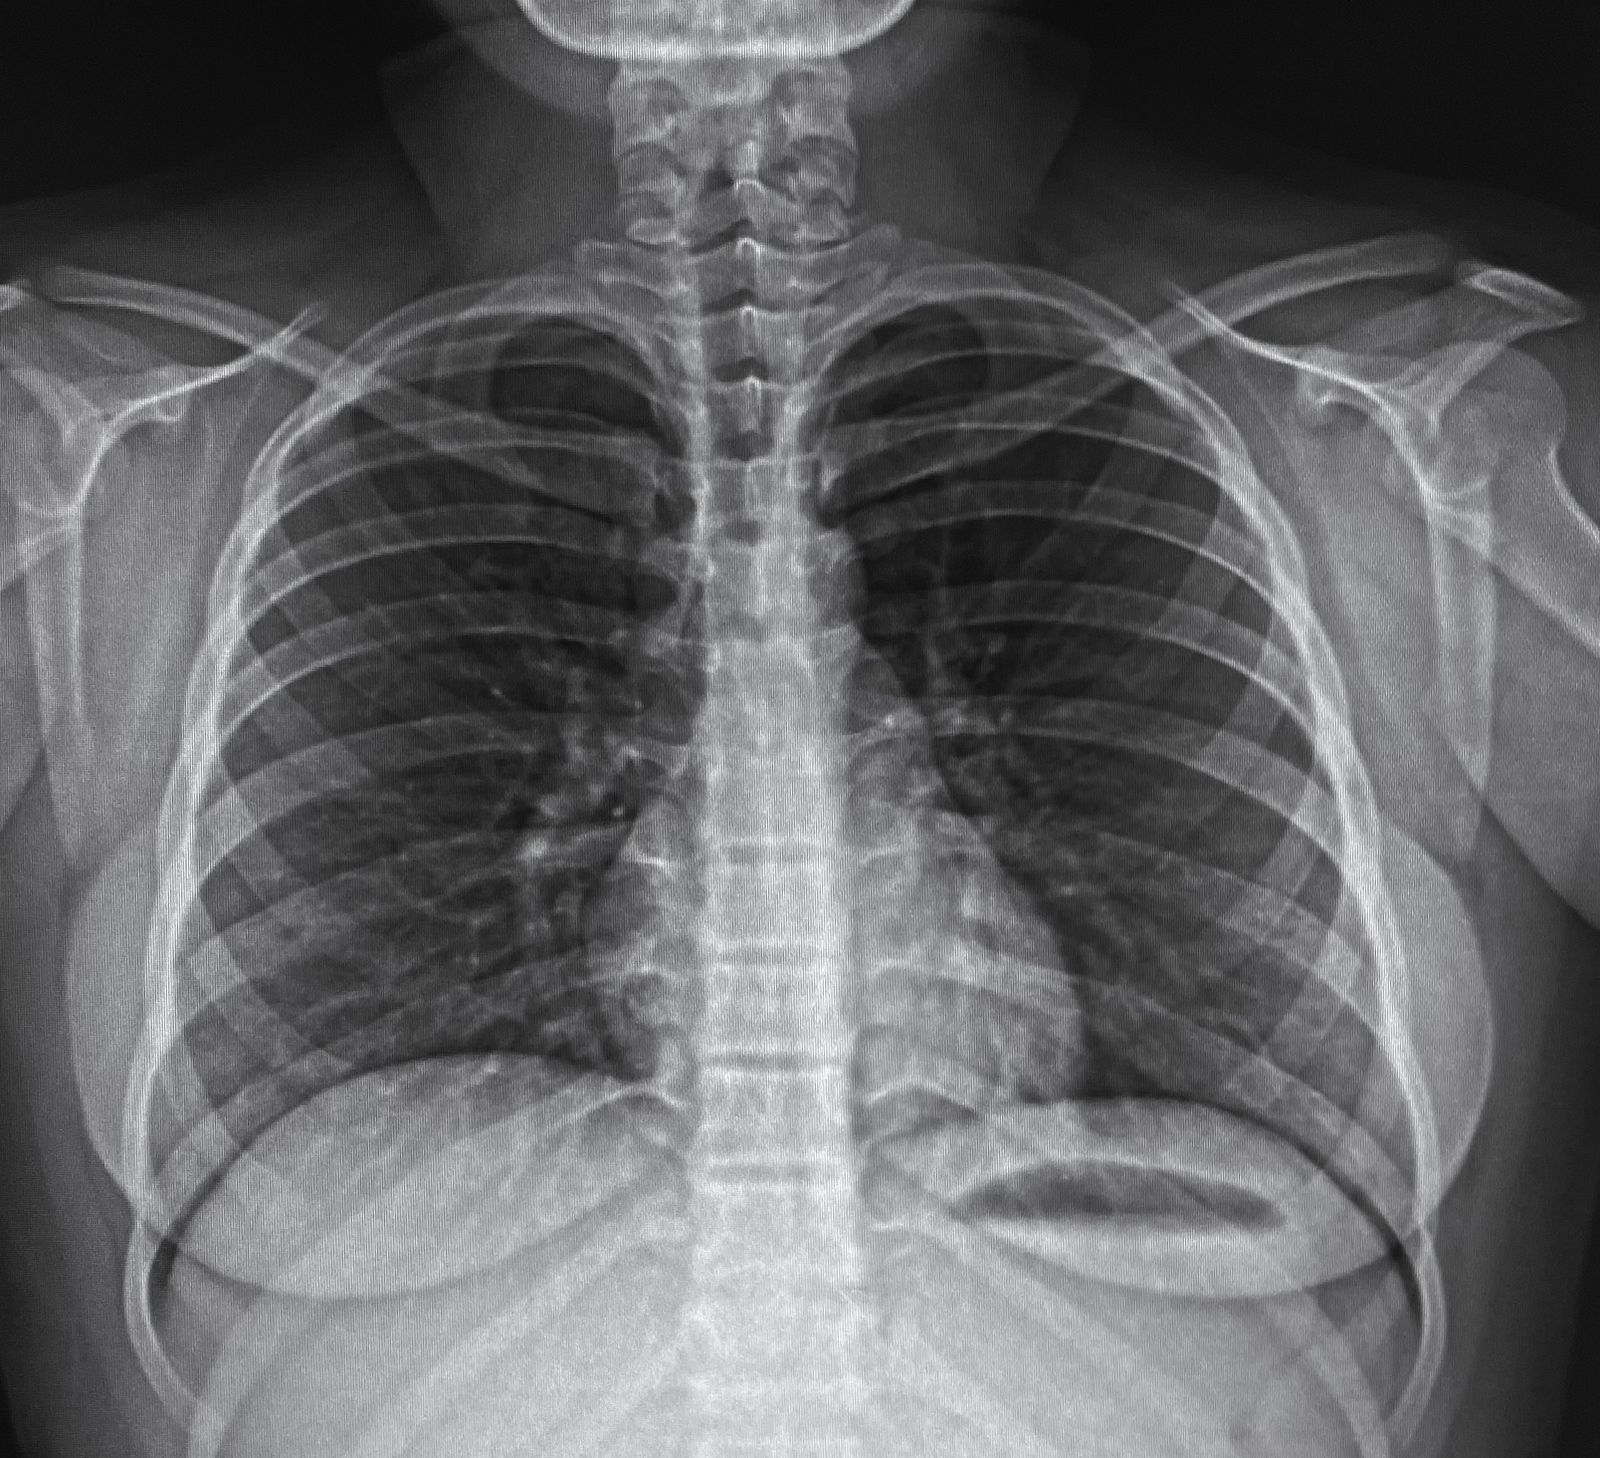

RADIOGRAFÍAS DIGITALES

Radiografías de todas las regiones del cuerpo con imágenes nítidas y detalladas.

- Torax